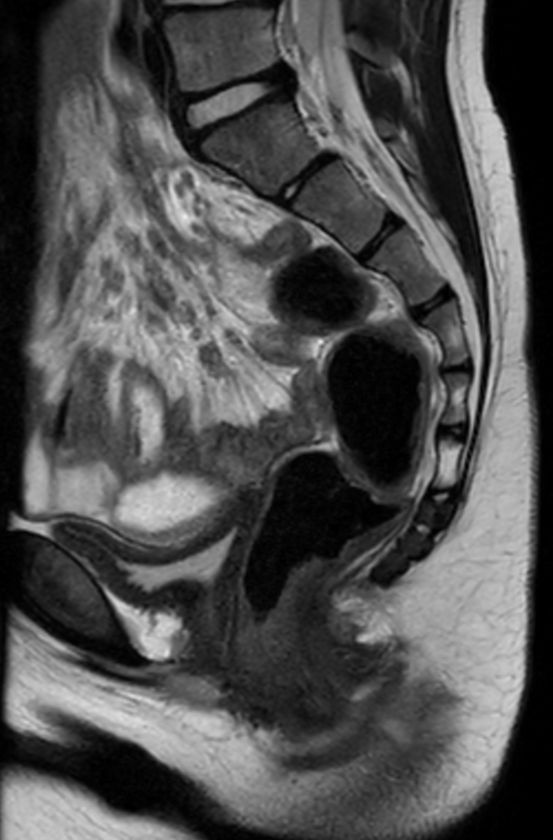

8 years old pediatric patient with a fistula in the pelvis. MultiVane XD is used to achieve high resolution diagnostic images, even in the case of severe patient motion. Integration of Compressed SENSE acceleration technique enables speeding up of the entire exam.

Sagittal T2w TSE